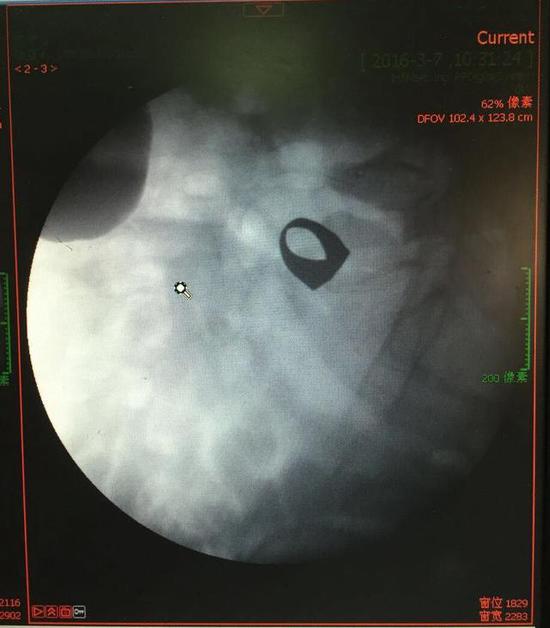

考虑到患者年龄较大,有冠心病,曾经中过风,高血压极高危级,遂把老人安排在带有监护的病房,立即给予吸氧,补液等治疗。医院立刻开启绿色通道,医护人员专门陪伴病人做了增强CT,腹部平片,和碘水造影,确定戒指的位置。检查结果提示戒指位于右下腹小肠内,距回盲瓣体表投影约5cm。

3月9日,夏泽锋教授细心的给病人做结肠镜检查,找到回盲瓣,调整结肠镜镜头,快速的进入小肠。结肠镜缓缓上行至距离回盲瓣5cm的小肠,没有戒指。继续上行,至20cm的地方,仍然没有找到戒指。

此时一个又一个大大的疑问出现在每个在场的医护人员脑海中,戒指还在小肠里吗?戒指在哪个位置呢?夏教授立刻联系放射科,拍片子,发现戒指已经移动了,从右侧移动到了左侧去了。放射科医师建议,戒指有可能会继续沿肠道下行,如果过了回盲瓣,就可以自行排出,免除手术痛苦。教授们采纳了这个意见,立即给予促进胃肠道动力药,枸橼酸莫沙必利片,每日口服三次,另外配合灌肠治疗,促进肠道蠕动,利于戒指排出。